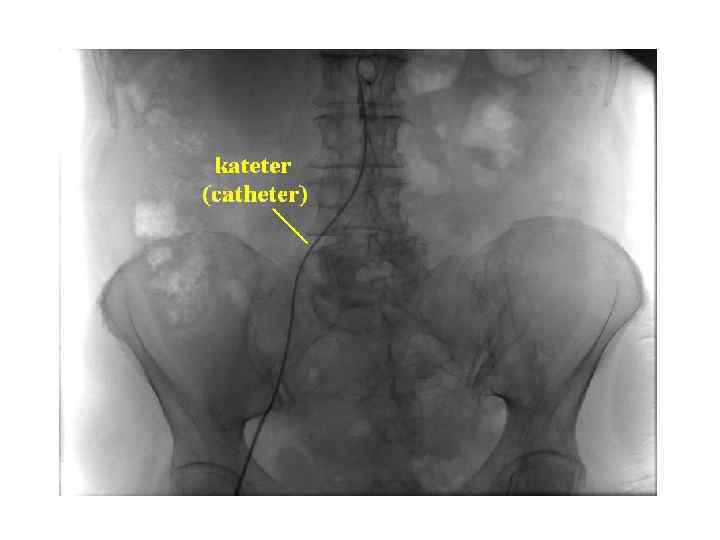

Пациент укладывается на ангиографический стол, фиксируется и подключается к кардиомонитору, в вену устанавливается Пациент укладывается на ангиографический стол, фиксируется и подключается к кардиомонитору, в вену устанавливается катетер для инъекций. Перед исследованием через катетер проводится премедикация: введение антигистаминных препаратов (профилактика аллергических реакций), транквилизаторов, анальгеников. Исследование проводится путем пункции (прокола) сосуда с последующей катетеризацией (введением в сосуд специального катетера, через который затем будет вводиться контрастное вещество (препарат йода)). Чаще всего проводят катетеризацию бедренной артерии. Все действия внутри сосуда осуществляются под контролем рентгенотелевидения. По окончании исследования на область пункции на сутки накладывают давящую повязку. • После проведения ангиографии необходимо пить большое количество жидкости, чтобы ускорить выведение йода и медикаментов из организма.